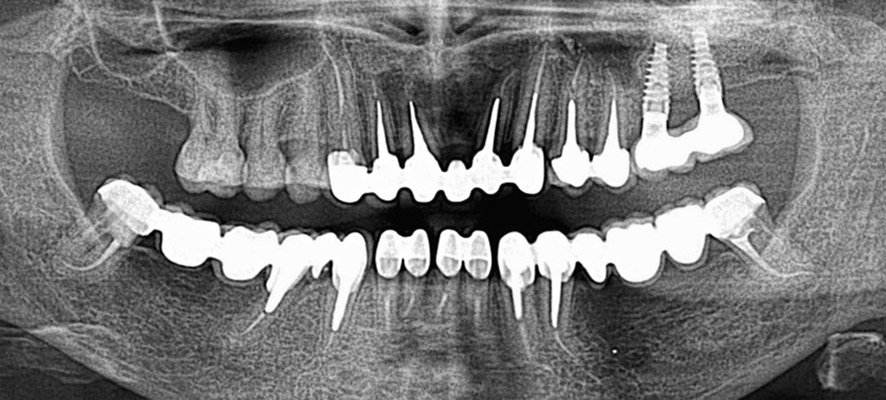

TREATMENT OF ROOT CANALS

In terms of endodontic therapy we treat root canals by hand or mechanic techniques according to latest research. The use of a microscope significantly enhances the quality of our work. We invest into equipment and instruments of high quality and so we guarantee high efficiency of endodontic treatment.

After-endodontic treatment is performed by filling the endodontic treated tooth with fiber posts or laboratory prepared metal posts.